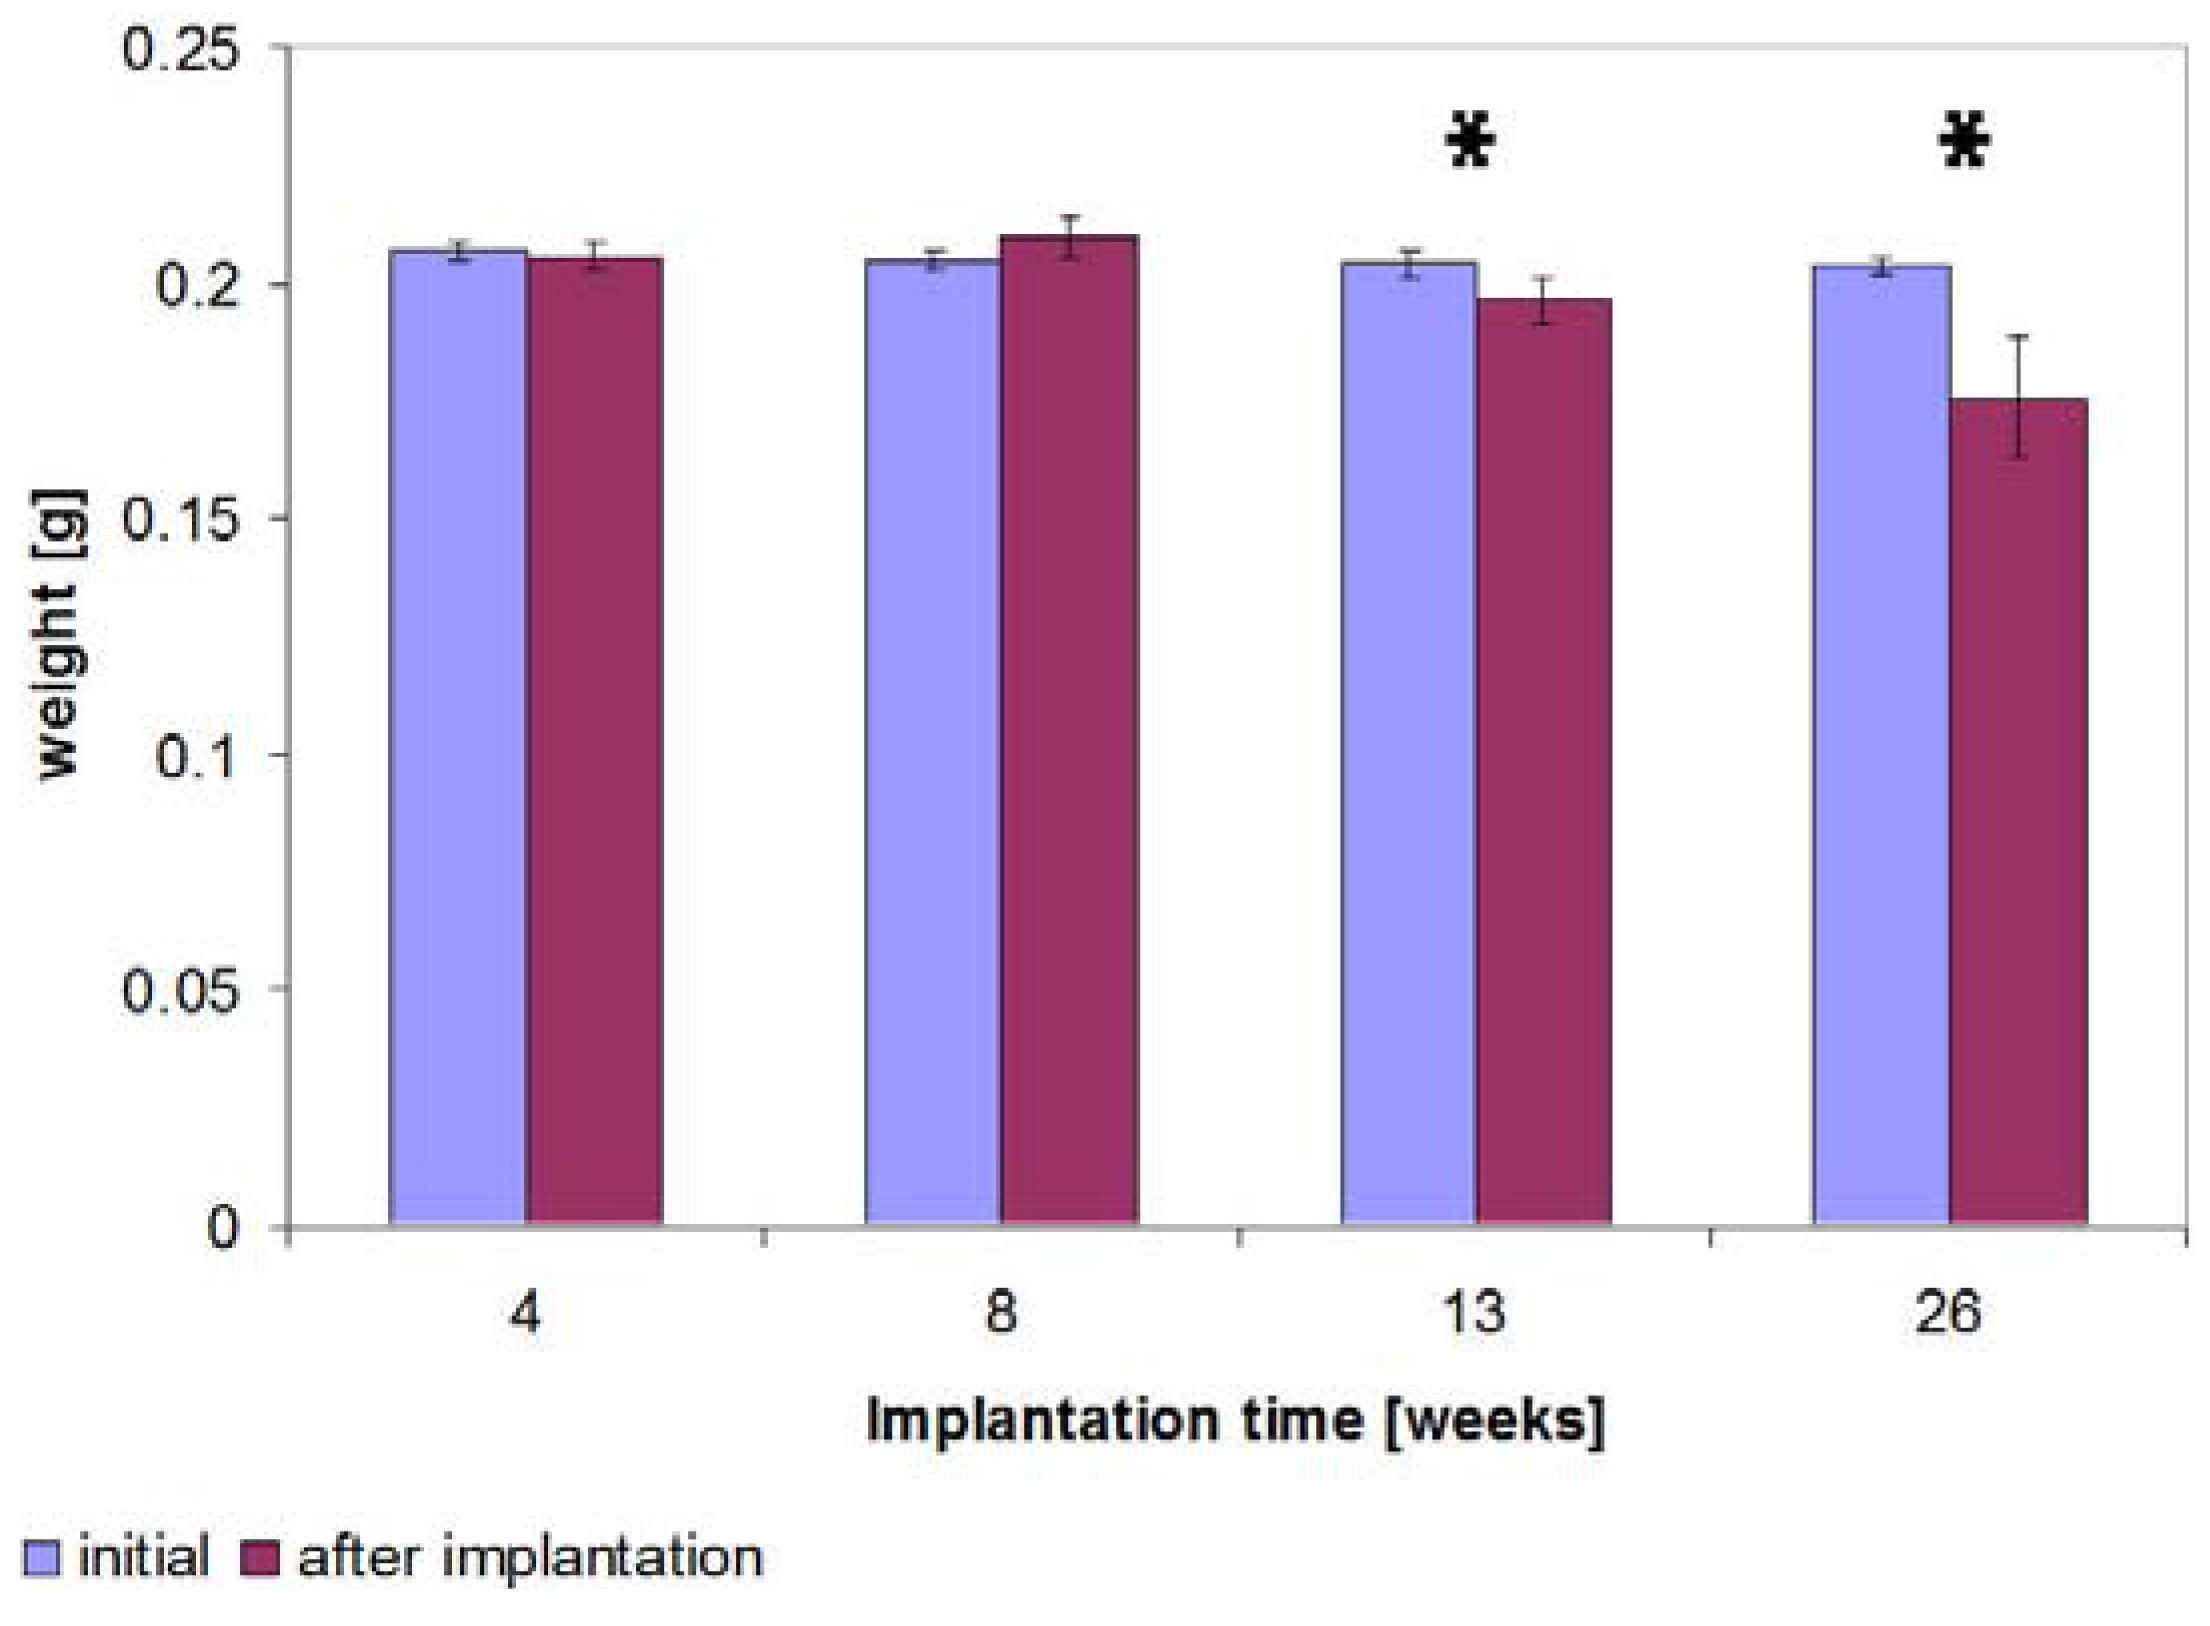

2.7. Determination of the Weight

3.3.5. Determination of the Weight